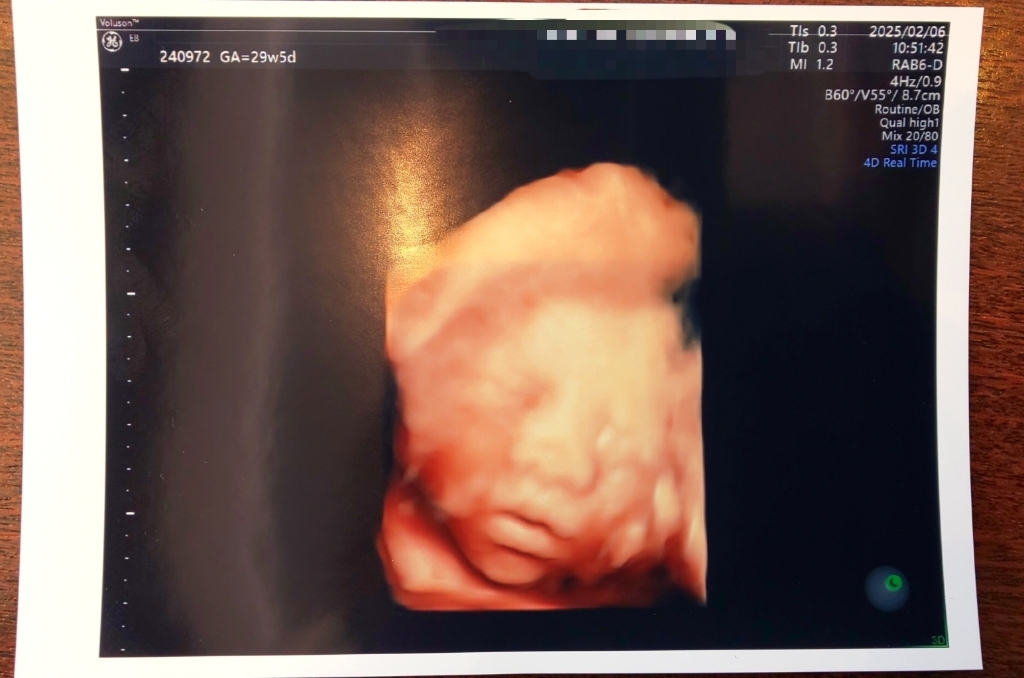

気になる4Dエコーですが、案の定こちゃは私のへそ右側部分に頭が固定されているようです。骨盤の隅、お腹の壁に顔をべったりくっつけているようで、その状態で口元に両手を持って来てもごもご動くので痛いぐらいの胎動を感じています。今日もそんな感じで壁に顔をくっつけていたので鼻がぺちゃんこの状態になってました笑

前回顔を見たときよりもふっくらしてて可愛いです。そして口元が私にそっくり…笑 エコー写真を寝袋君にも見てもらいましたが、口元は完全にらららだねーと言ってました(寝袋君は唇が薄くて受け口)口元と顎のラインは私に似てるみたいです。まばたきもして、口をパクパクさせて、口元に両手持ってきてもぞもぞしてて、胎動激しい暴れん坊だけど元気だな~と思ってエコー見てました。それにしても口かわいいな~